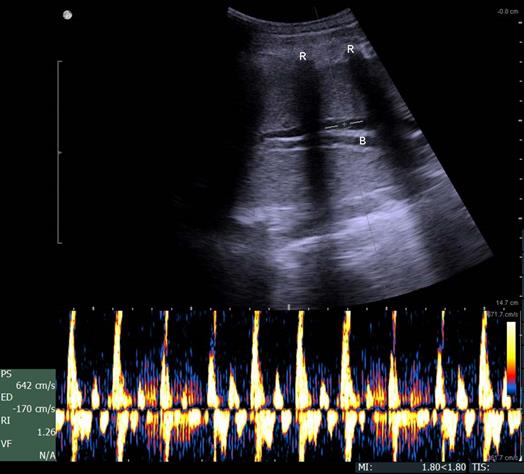

At this point, lung sonography showed few B-lines and a slight increase of pleura thickening in absence of subpleural consolidations or pleural effusions of the previously flooded lung compared to the right lung (Fig. 7).

Figure 7

Lung sonography 30 minutes after deflooding and two-lung ventilation. Illustrated are the left lung (filled with saline over 3 hours, A) and the right lung (only ventilated, B). The left lung shows a slightly thickened pleural line and few B-lines (stars); the right lung presents a sharp pleural line (arrow) and no B-lines.